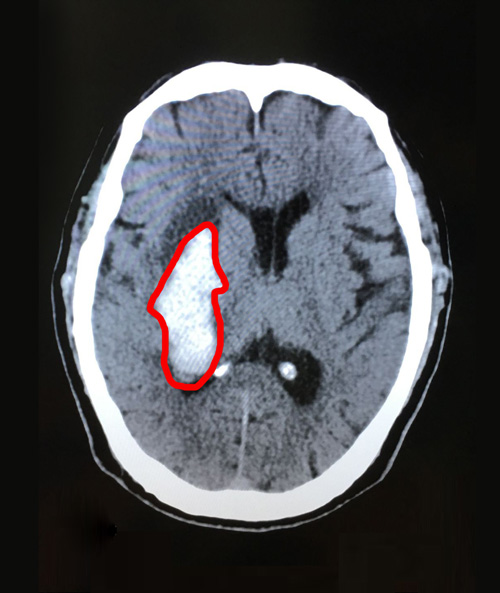

术前影像:右侧基底节区急性脑出血,右侧脑室后角少量积血

术后影像:脑出血引流术后,几乎看不到血肿残余